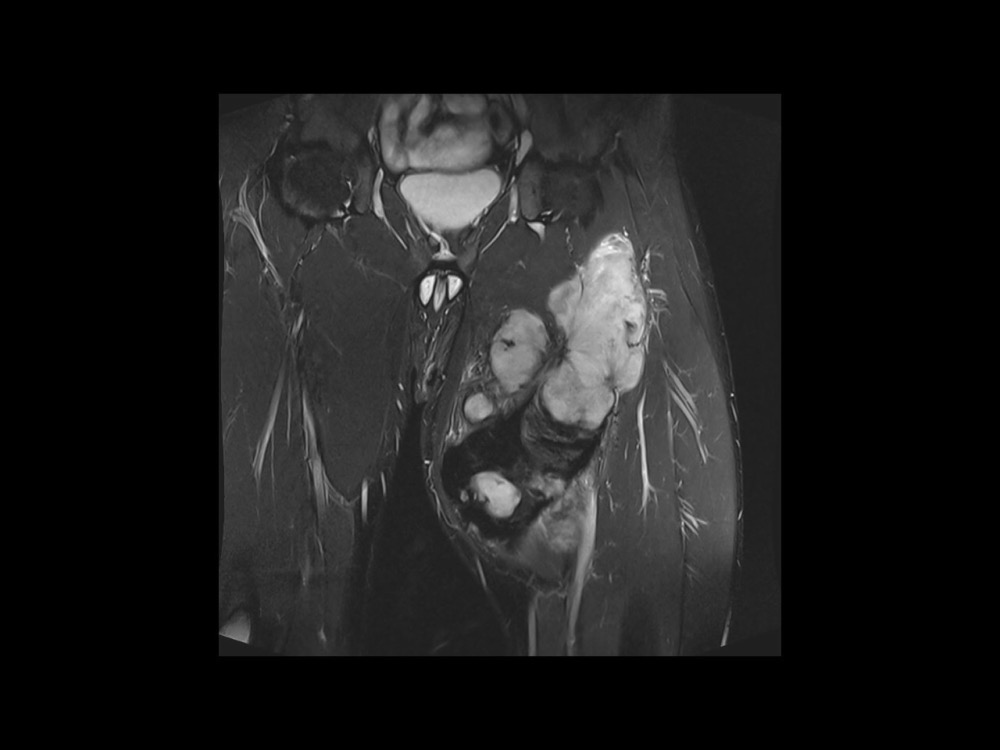

Moalla / Mihoubi-Bouvier / Drapé 18/05/2022